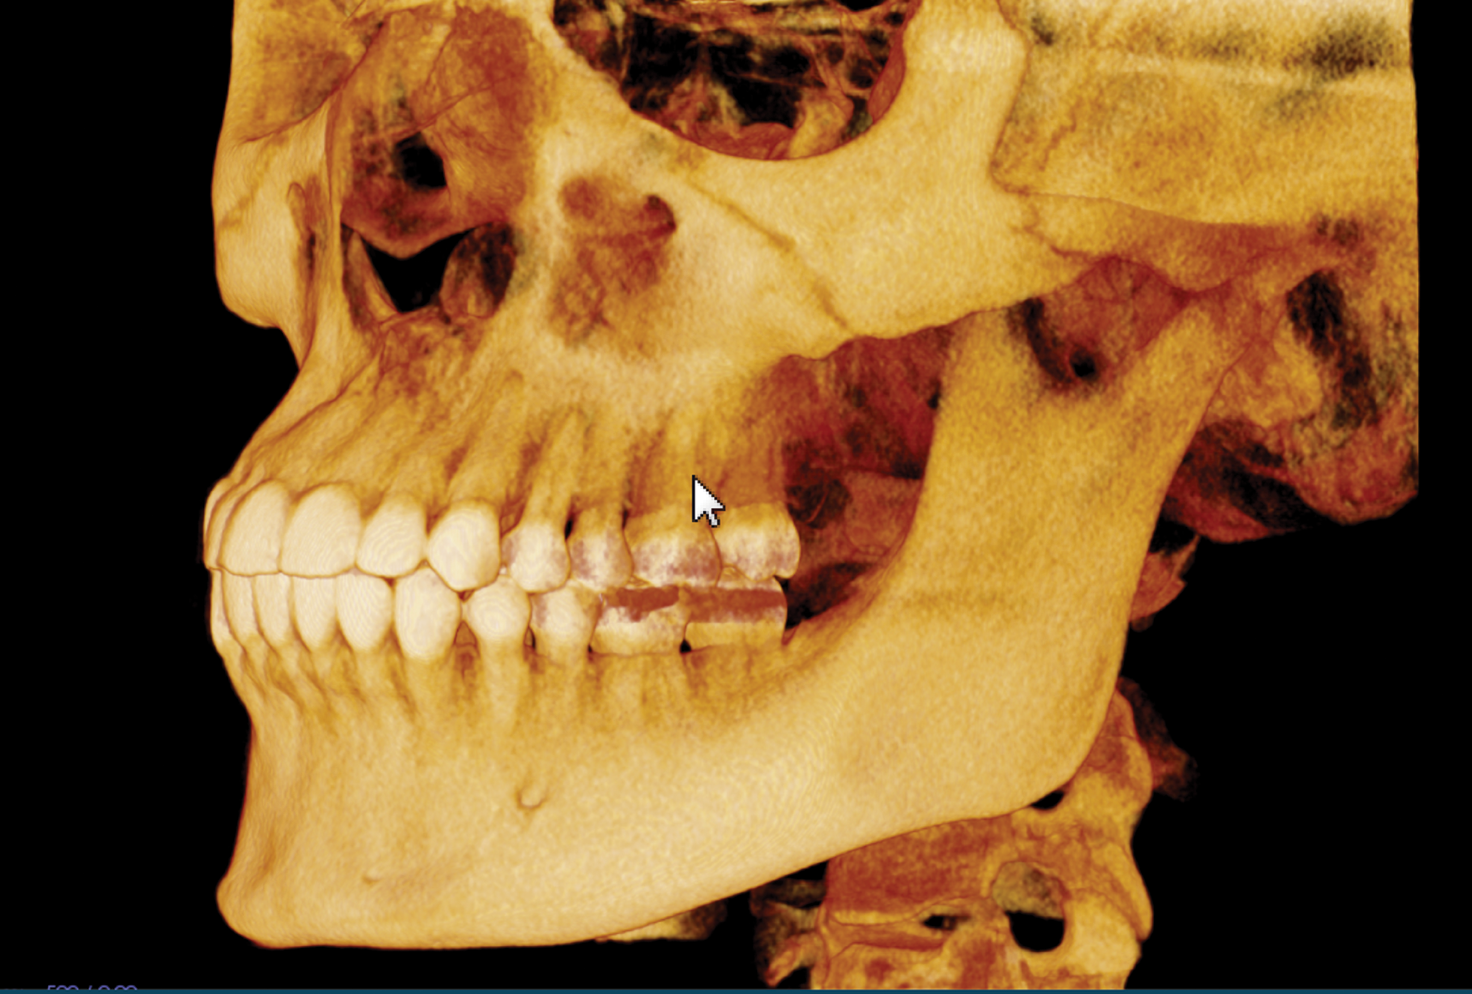

I extracted the tooth and used autogenous platelet-rich fibrin (PRF) and bone graft to preserve the space. After the extraction, I allowed healing time (Fig. 3). Approximately four months later, we placed the implant.

Fig. 3 Fig. 4

I started with the capture of a post-extraction i-CAT CBCT scan (Fig. 4), focusing in on the area of interest. I reviewed the implant site carefully and also used the Hounsfield tool in Tx STUDIO to assess the density of the area, which was 662 HU (Fig. 5).